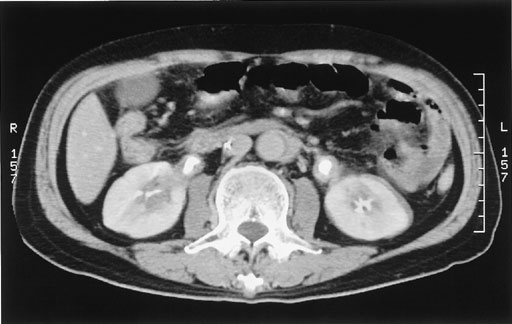

図6:

腹部大動脈周囲,腎被膜周囲,尿管周囲に瀰漫性濃度上昇域を認める.